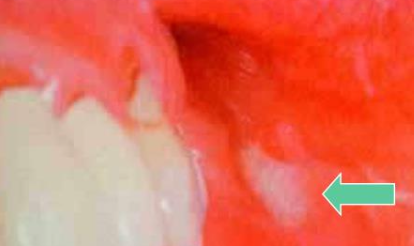

Excretory duct Mucoepidermoid carcinoma1st 2-70y

• Radio relation

• parotid gland (60-70%) → Palate

• GENE:MECT1-MAML2 fusion

• 缺乏capsule、infiltrating border

• 分成三種細胞: Squamous cell, Mucin-secreting cell, intermediate hybrids(前二之間,前驅)